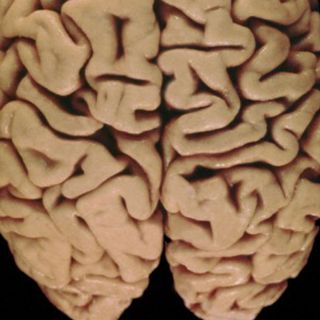

CIUDAD DE MÉXICO (06/FEB/2011).- Los bajos niveles de glucosa pueden estar relacionados con la muerte neuronal, y esto a su vez afectar el estado de conciencia, memoria o razonamiento de las personas. Así lo determina una investigación que actualmente realizan científicos del Instituto de Fisiología Celular de la Universidad Nacional Autónoma de México (UNAM).

“Cuando éstos se prolongan el resultado es muerte neuronal. Lo anterior afecta al cerebro en zonas sensibles a la falta de glucosa, como la corteza cerebral encargada de las actividades cognitivas, y el hipocampo, cuyas funciones se relacionan con memoria y aprendizaje.”, reiteró la doctora Massieu-Trigo.